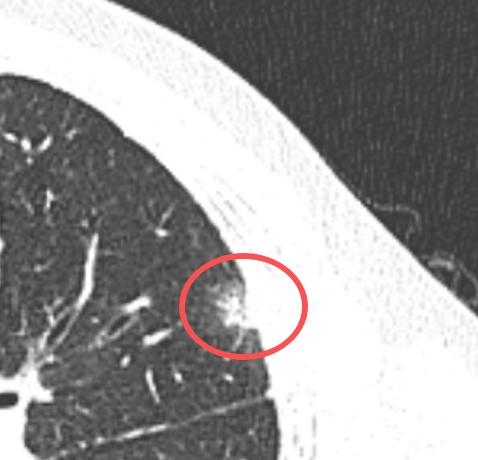

肺结节什么情况下才叫“有进展”?我们在观察期间,如果发现肺结节有变化,才会考虑进

发现肺小结节后,最主要的措施就是定期复查、持续观察。很多朋友会问我:在观察期间,